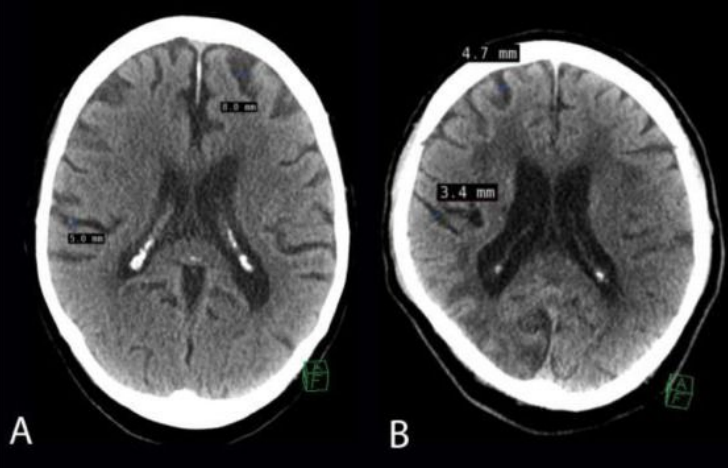

Cerebral Ventricles

● 4 ventricles: 2 lateral, 3rd ventricle, 4th ventricle

● Each contain choroid plexus (produces CSF)

CSF: cerebrospinal fluid [plasma] provides nourishment, shock absorber, protection/waste removal

● Blockage in any of these can result in pressure on brain